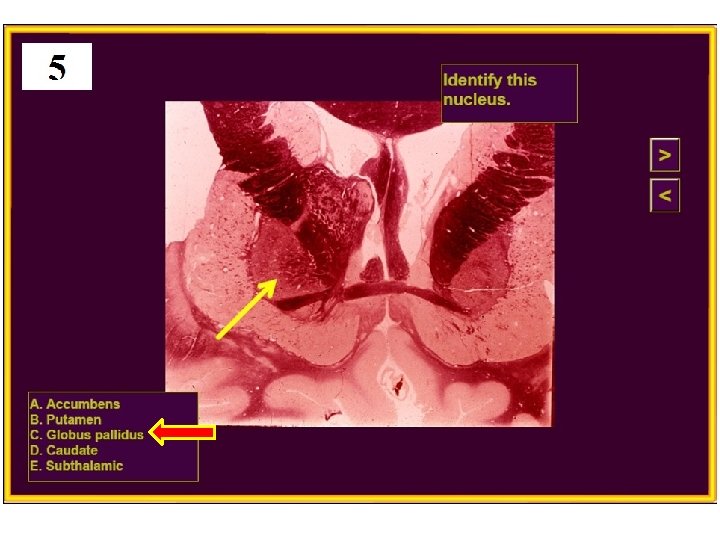

20. Huntington’s disease is caused by degeneration of which nucleus? A) Subthalamic B) Globus pallidus C) Substantia nigra D) Caudate E) VPL